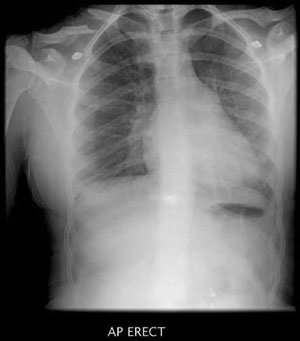

Excluding a significant pelvic fracture is an essential part of any trauma assessment.

An AP pelvis x-ray is required in all trauma patients except in those who are:

This image is required early (with lateral cervical spine) if there is unexplained haemodynamic instability.

If there is any doubt, the pelvis AP X-Ray should be performed as part of the initial trauma series.